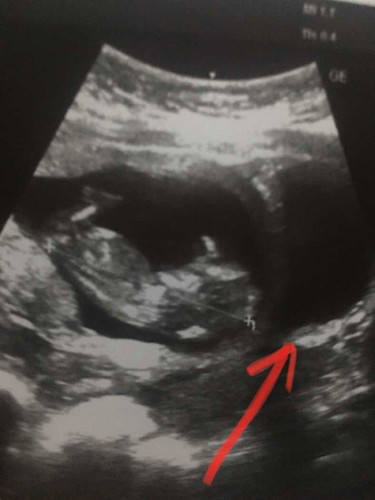

สอบถามแม่ๆบ้านอื่นที่มีประสบการณ์ลูกแฝดหน่อยค่ะ ตอนนี้13w5d รพ.ซาวด์ให้มี2ช่องแบบนี้แฝดมั้ยคะ เพราะน้องที่มีแฝดบอกว่ามีโอกาสเป็นไปได้ ส่วนน้องอีกคนบอกว่าให้ไปซาวด์คลีนิกเลยเพราะบางรพ.ก็ไม่บอกว่าเราแฝดมั้ยให้เราไปซาวด์คลีนิกถ้าแฝดก็ให้ไปแจ้งรพ.ที่ฝากอีกมีจิงมั้ยคะ สอบถามแม่ๆบ้านแฝดทีนะคะ ปล.ที่บ้านแม่มีกรรมพันธุ์ค่ะ คุณยายแม่มีลูกแฝด1คู่คือน้าชายแต่ลูกๆของยายไม่มีใครได้แฝดเลยค่ะมีโอกาสที่น้องจะมาติดที่รุ่นของแม่มั้ยคะ #ขอบคณสำหรับคำตอบล่วงหน้านะคะ 🙏